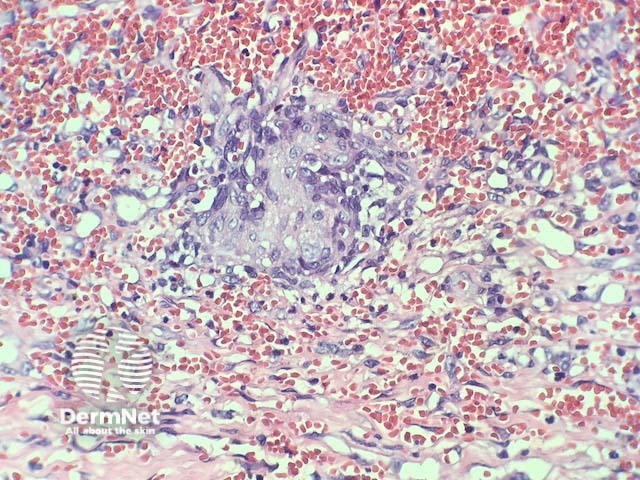

In verrucous haemangioma, the histopathology shows irregular papillomatosis, acanthosis and hyperkeratosis of the epidermis. The dermis shows multiple, thin-walled, dilated blood-filled spaces. Intravascular thrombosis with recanalisation and haemorrhage can be seen (figures 1–5).

Figure 1